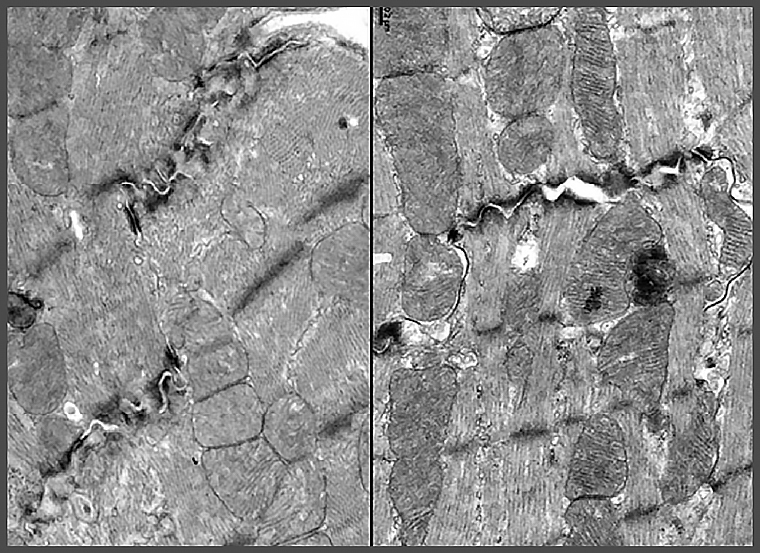

▲左圖為使用小紅莓治療後的小鼠心肌細胞,黑色類似峽谷的地方為心肌受損;右圖使用橙皮素後可看見受損的地方慢慢復原。(圖/陽明交大提供)

研究團隊發現,小紅莓會抑制心肌細胞中長壽基因CISD2的表現,使粒線體與鈣離子調控失衡,導致心臟收縮與節律出現問題。相反地,橙皮素可以重新啟動長壽基因CISD2,減少心肌細胞受損。

令人振奮的是,橙皮素不僅能撐起心臟保護傘,在動物實驗中,小紅莓處理的長腫瘤小鼠,注射橙皮素後,不僅顯著改善心臟功能,腫瘤體積也明顯縮小,顯示橙皮素不會影響小紅莓的抗癌力。橙皮素對心肌細胞的保護作用,研究團隊也運用由美國史丹福大學所提供的人類誘導性多能幹細胞(iPSC)衍生的心肌細胞加以驗證,強化支持橙皮素臨床應用的潛力。